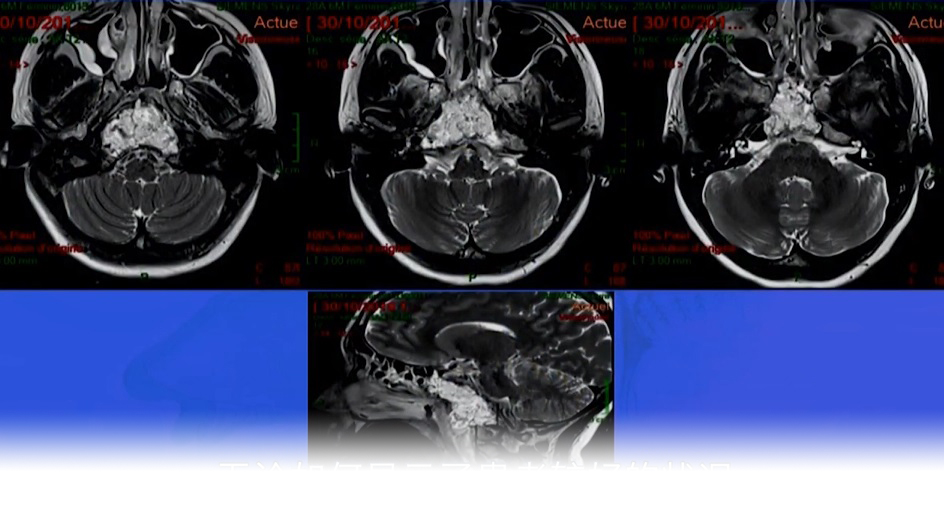

病情回顾:患者术前MRI和CT扫描显示,显示椎前、斜坡较大肿瘤,颅颈交界区CCJ较大脊索瘤,肿瘤体积126.2cm³,累及下斜坡、右侧岩尖(PA)、双侧枕髁(OC)、脊髓C1和齿状突,并从C0延伸到C6椎前间隙,呈现广泛浸润性生长。

图片术前MR

▼通过右侧内镜辅助远外侧经髁入路(EA-FLTA)切除颅颈交界处残余肿瘤(33.4 cm³)(图4D-F)。然后,进行枕颈融合术(OCF)(C0-C3-C4-C5)。

D-F:术中在CT引导神经导航下,进行EA-FLTA入路手术,显示进入斜坡(D)、齿状突(E)和对侧OC(F)的手术操作可行性。

▼术后MRI显示NTR(图4G-I)。

图片G-I:术后MR显示椎前、下斜坡和椎后的肿瘤被切除。